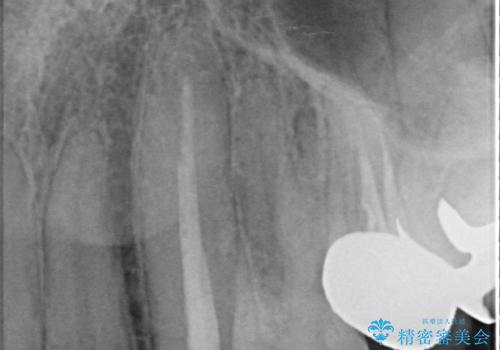

- 根管治療後歯が黄色くなってきたのでセラミックにしたいといらっしゃった方の症例です。

再根管治療後、オールセラミッククラウン(スペシャル)による補綴を行いました。